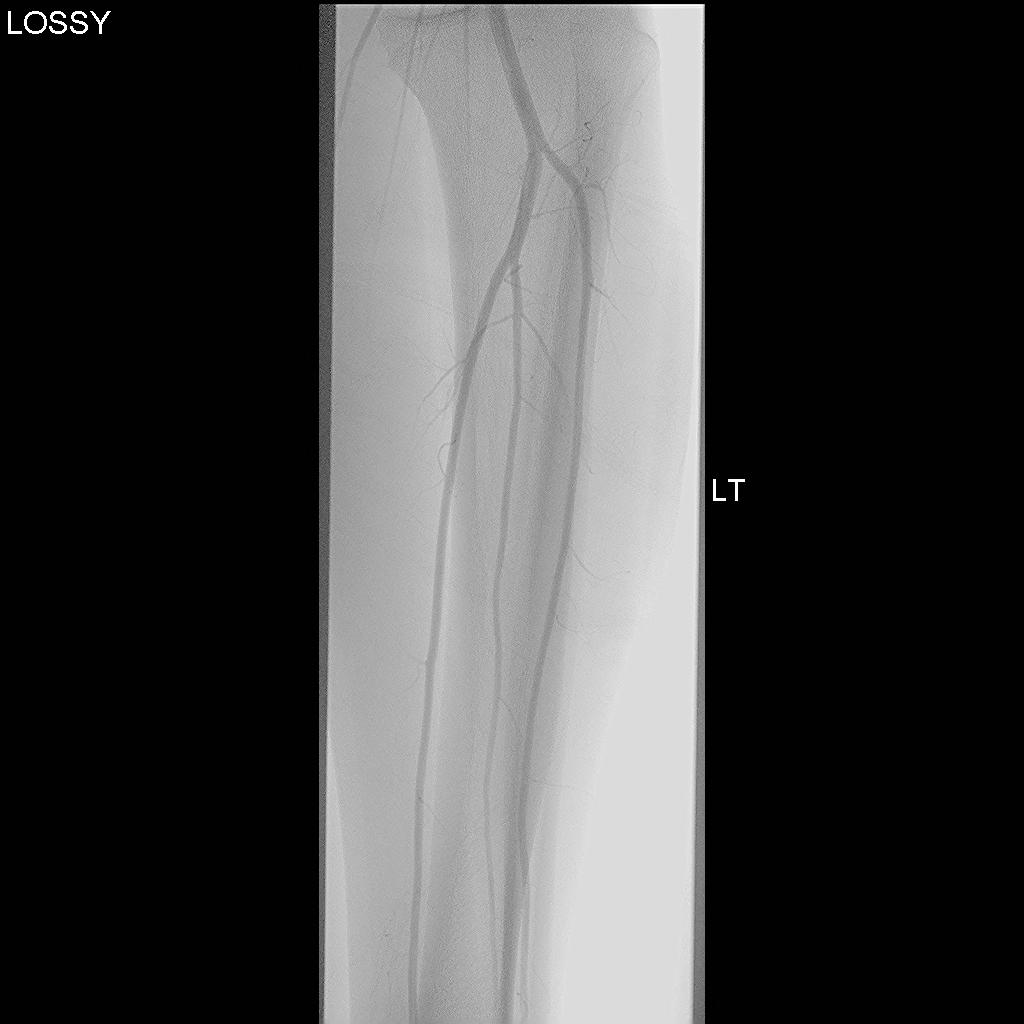

Normal CT angiogram Popliteal artery stenosis following knee dislocation

Popliteal artery transection following left knee dislocation

Advantages

- readily available, non invasive

- extremely accurate

- also used confirm the site and mechanism of injury

- multi-detector CT

- 100% sensitive and specific in detecting clinically significant arterial injury

Gakhal et al. Vascular and Interventional Radiology 2009

- CTA signs of lower extremity vascular trauma

Normal angiogram

Popliteal artery injury on angiogram